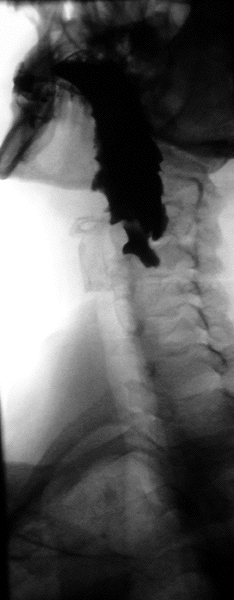

The second patient told me about the testing he went through. Apparently there is some kind of barium x-ray that can be taken that shows places in the esophagus and stomach affected by acid reflux. He was also put on medication. He told me today that if he misses his medication it makes for a long and painful day from heartburn.